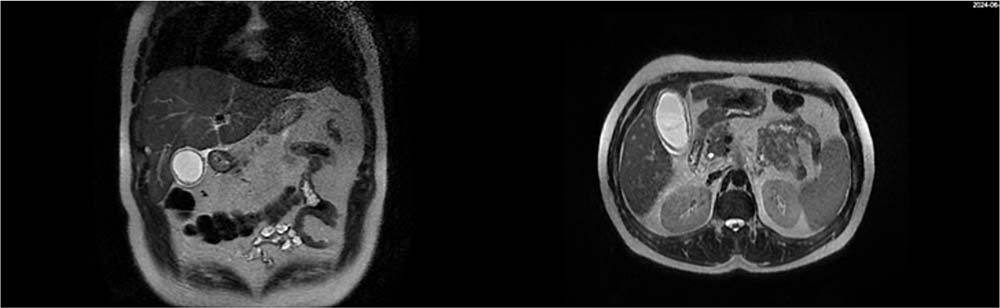

病史摘要:15 岁女性学生,因“乏力伴皮肤黄染 1 周”入院,既往体健,无饮酒及肝毒性暴露史。 诊疗过程:查体见神志清但反应迟钝,球结膜水肿,皮肤巩膜重度黄染,腹部膨隆有移动性浊音。检验显示肝功能多项指标异常,血氨升高,血常规部分异常,凝血功能异常,铜蓝蛋白稍低,甲状腺功能异常,多种病毒学及自身免疫肝病抗体阴性。腹部增强 CT 及核磁有异常表现。追问病史,结合检查怀疑肝豆状核变性急性肝衰竭